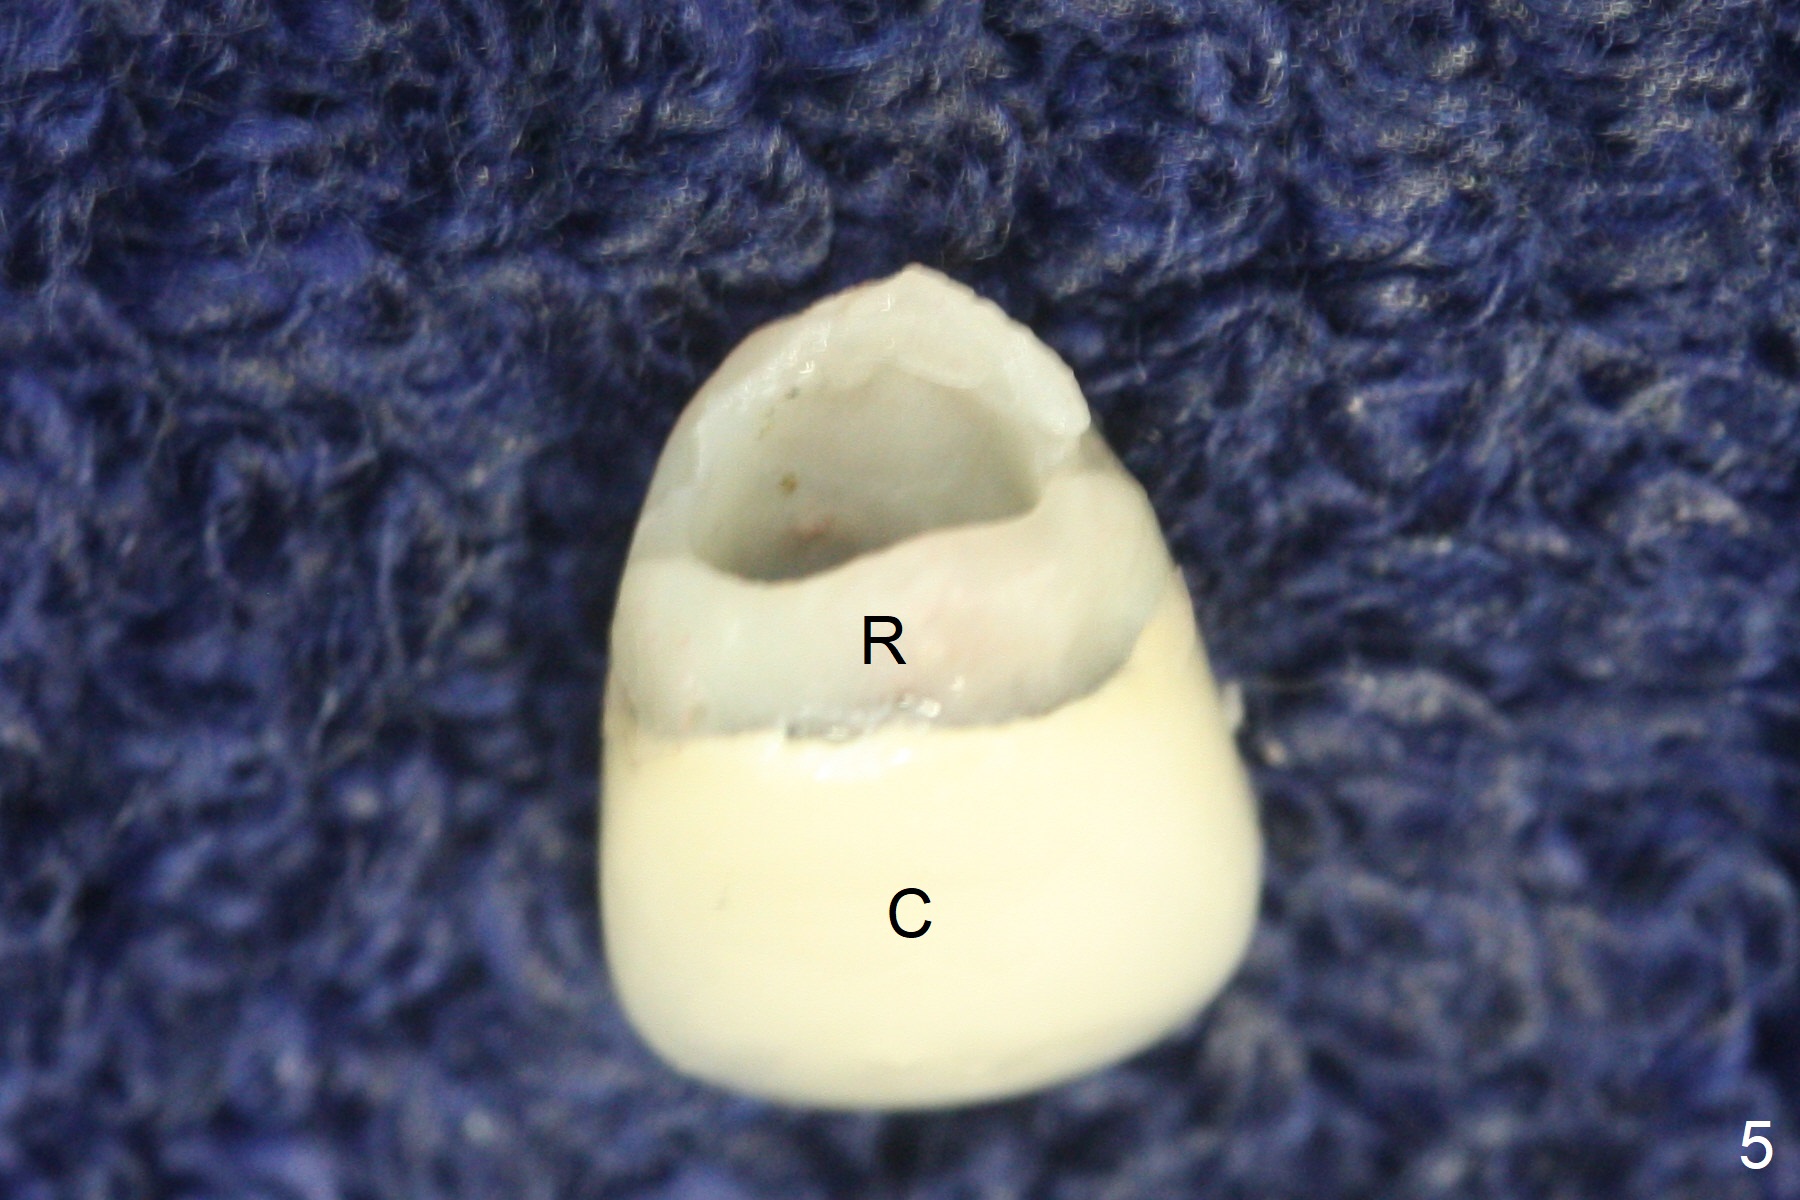

When the patient returns, the crown at #10 has displaced incisally (Fig.1,2 arrow). The initial depth is 15 mm (Fig.3, palatal gingival margin). After a 3.8x12 mm SM implant is placed (Fig.4), allograft is packed in the peri-implant space (*, as compared to Fig.3) and a 3.9x4(3) mm abutment is placed (A). More allograft is placed in the peri-abutment space (Fig.6 *). The existing crown (Fig.4,5 C) is hollowed, relined (R) and used as an immediate provisional (Fig.7-9). The patient is pleased with the appearance of the apically-repositioned provisional (Fig.7 arrow). She returns for impression 3.5 months postop (Fig.10). After change of abutment to 3.9x4(4.5) mm and new provisional, impression is retaken 5 months postop (Fig.11,12). It appears that the implant is palatally placed and a little large for the site (Fig.11 (B: buccal); Fig.12 (^: thin layer of the palatal plate)). If an angled abutment were used, a screw-retained crown might have been feasible. Due to the new provisional, the gingiva looks healthy when a permanent crown is cemented (Fig.13).